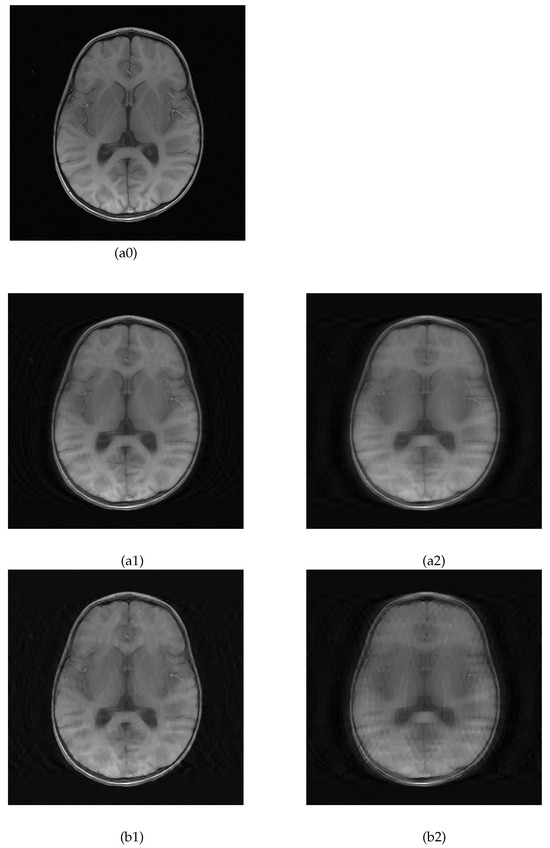

5.2. MRI Image Recovery

| Brain A | 27.7 | 24.1 | 0.642 | 0.524 | 26.7 | 22.3 | 0.637 | 0.493 |

| Brain B | 27.7 | 24.6 | 0.668 | 0.494 | 26.8 | 22.7 | 0.644 | 0.474 |